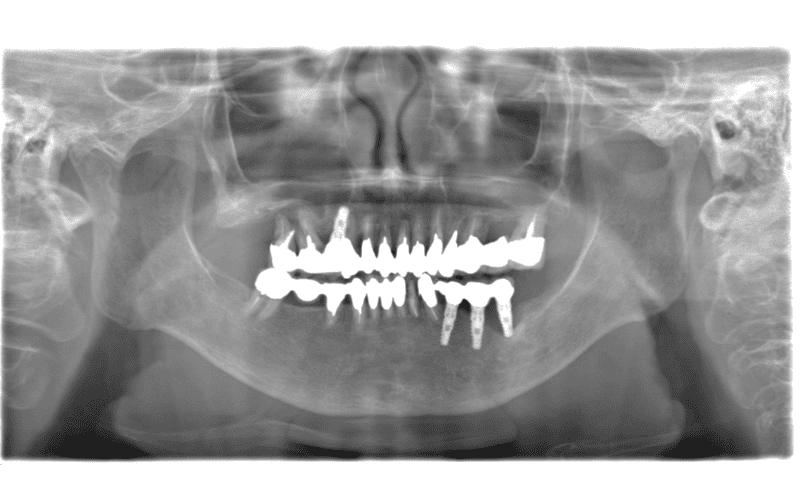

主訴 左上のセラミックの歯の歯ぐきが下がって変色した歯が出てきて見た目が気になるのでやり直したい。 性別 女性 年齢 50代 症例概要・補綴専門医としての分析 ・50代女性

・左上5番にオールセラミッククラウンが装着されている。

左上4番にはインプラントによるオールセラミッククラウンが装着されている。

頬側の歯肉退縮が生じており歯頸部に黒変した歯質が露出して審美障害を生じている。

全体的な辺縁不適合が認められた。

セラミック咬合面には若干の咬耗が認められた。

左上5番頬側歯肉辺縁に発赤・腫脹は認められない。

エックス線から歯根に問題は認められなかった。

患者さんには、過度にブラッシングする習慣があり、ブラッシング圧とブラッシング時間のコントロールを指導した。

また、クレンチングの習癖があり、生活指導及びナイトガードの夜間使用をお願いしている。

これらのご指導・お願いが実施されることを前提に、咬合力の強くない女性であること、審美性を重視していることなどからモノリシックジルコニアクラウンではないジルコニアフレームにポーセレンを積層する方法、ジルコボンドクラウンにて再補綴することとした。